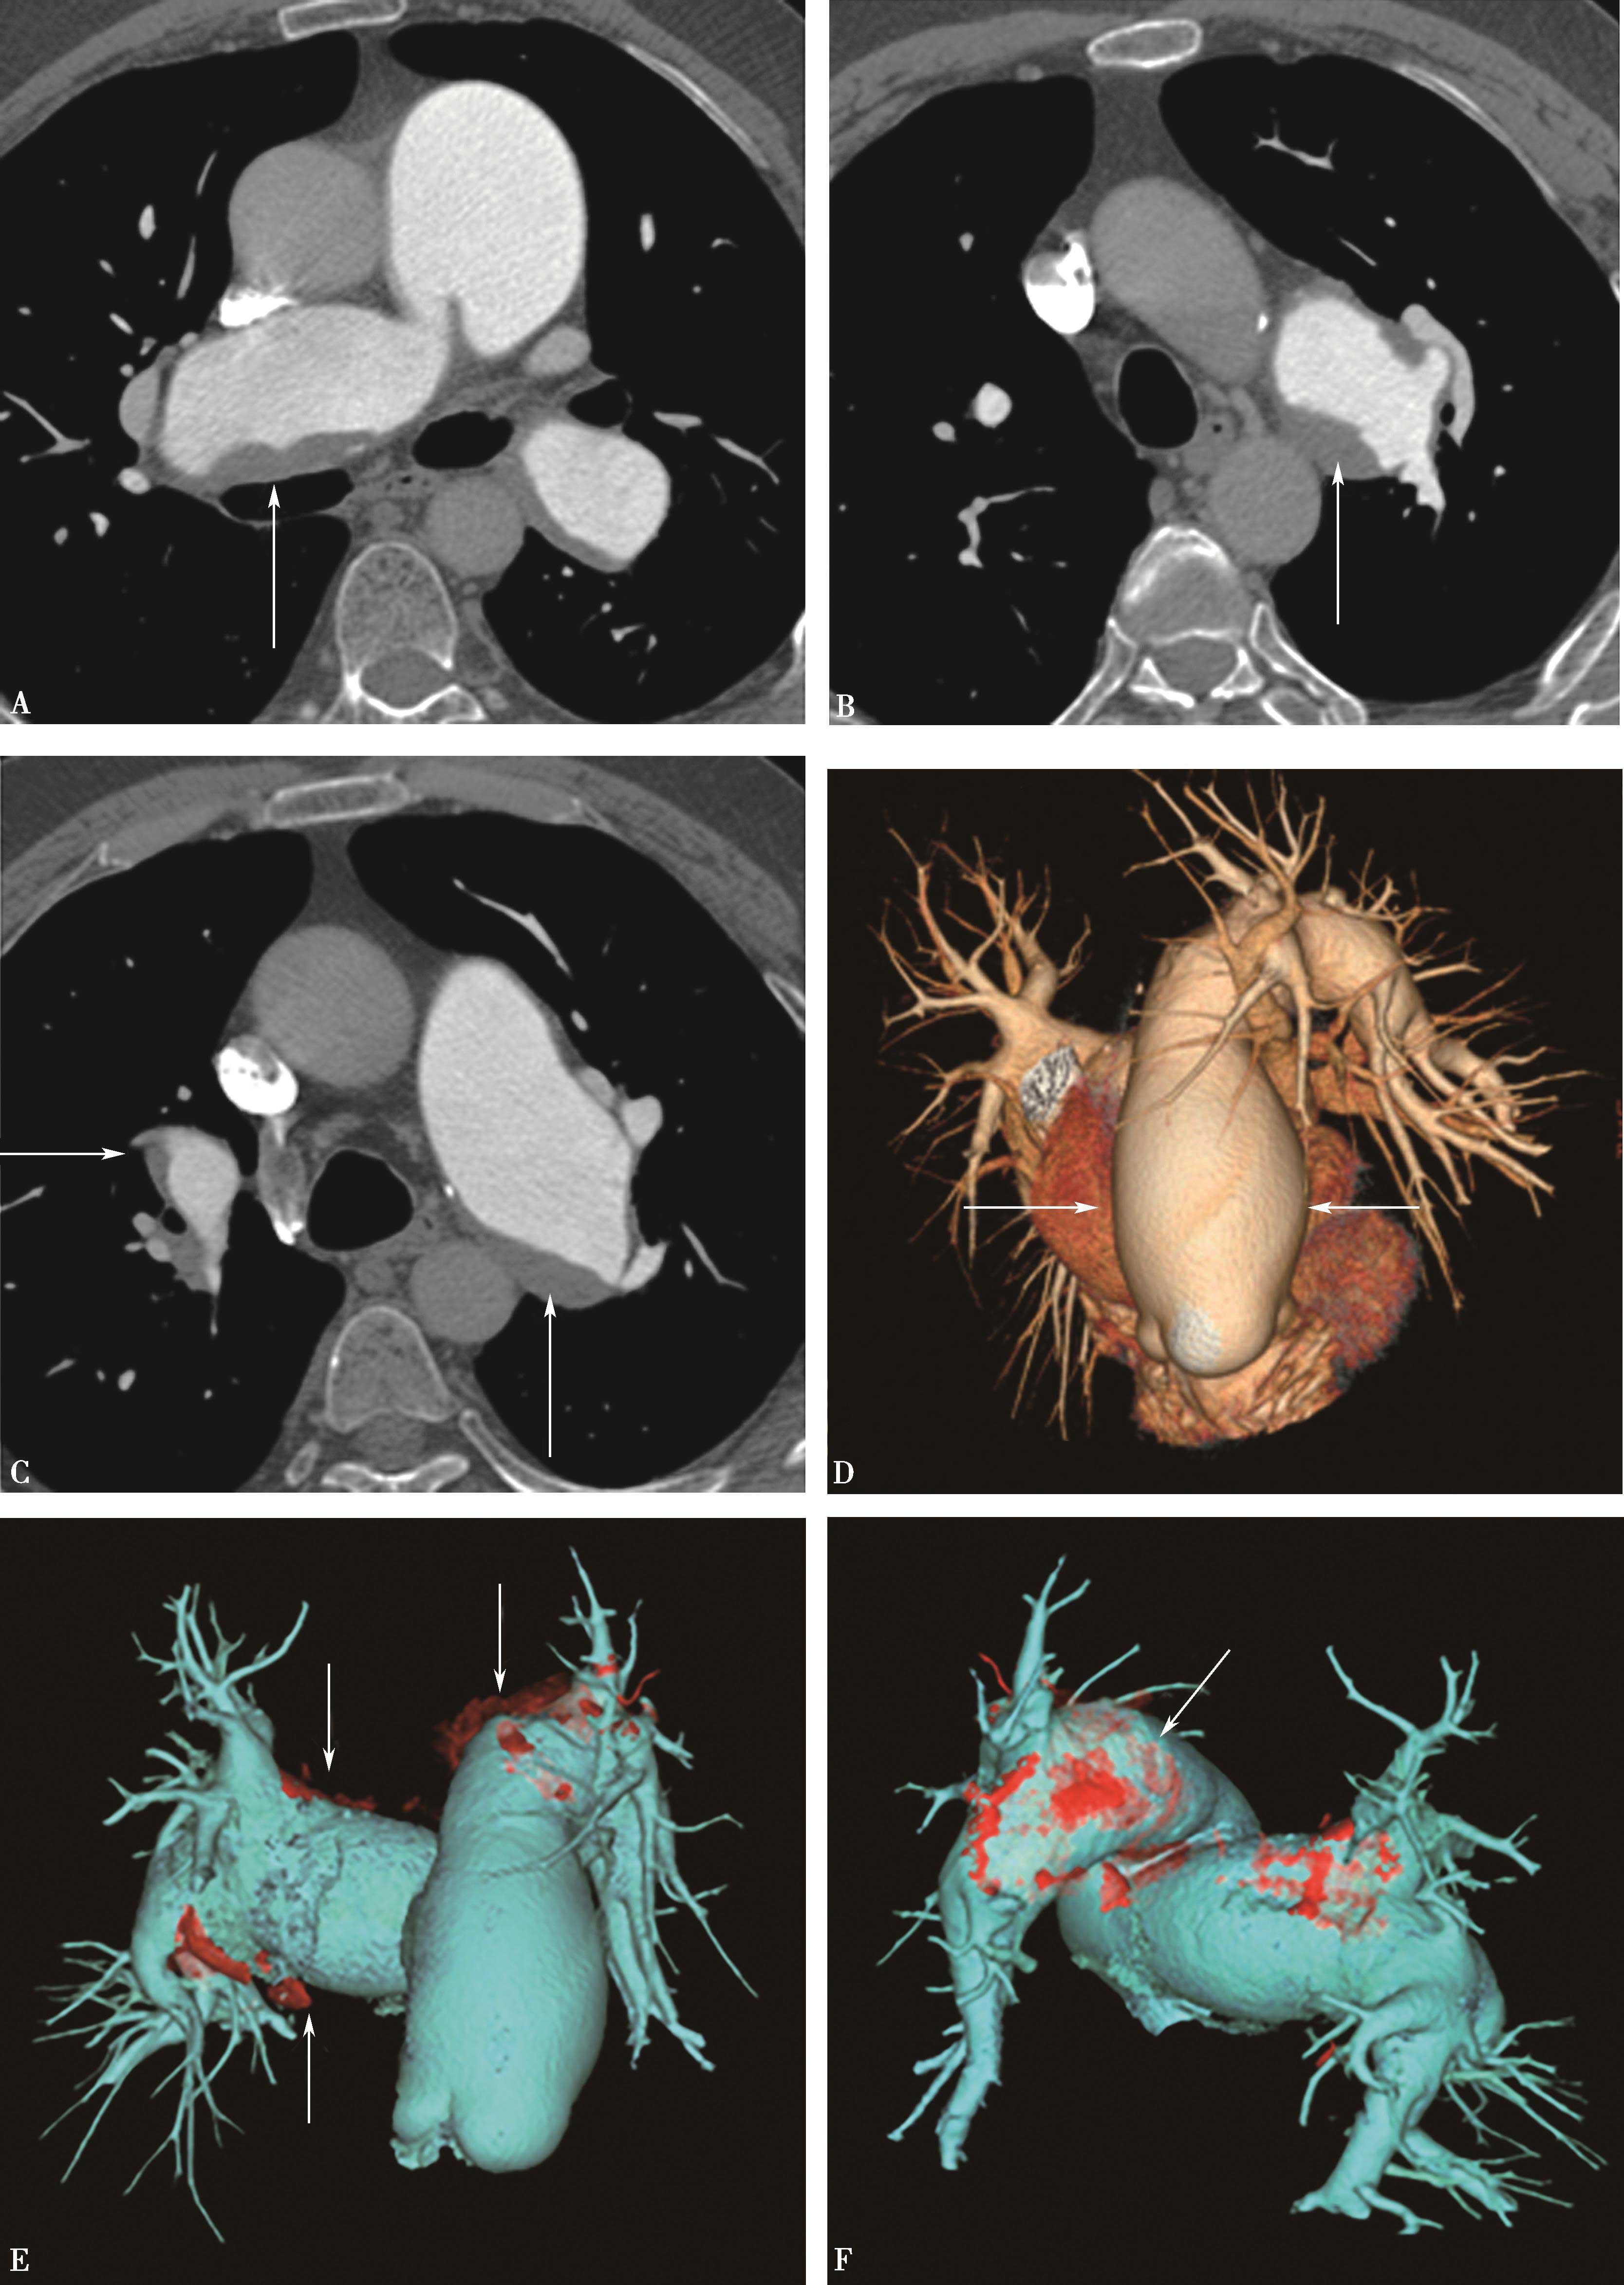

1)主肺动脉干或/和左右肺动脉干梭形瘤样扩张,腔内不同程度附壁血栓(图8-5-4)。

横断图像。A~C.主肺动脉、瘤样扩张,左右肺动脉瘤样扩张,不规则附壁血栓(↑);D~F.三维重建主肺动脉及左右肺动脉瘤样扩张,红色为附壁血栓(↑),波及肺叶分支;CT诊断:肺动脉瘤累及主肺动脉、左右肺动脉及叶分支,附壁血栓形成,病变性质考虑为白塞病